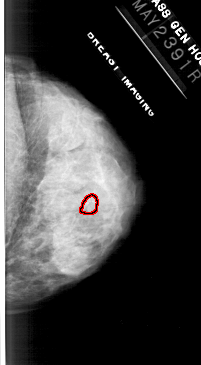

FILE: A_1113_1.RIGHT_MLO.OVERLAY

TOTAL_ABNORMALITIES 1

ABNORMALITY 1

LESION_TYPE CALCIFICATION TYPE PLEOMORPHIC DISTRIBUTION CLUSTERED

ASSESSMENT 4

SUBTLETY 3

PATHOLOGY MALIGNANT

TOTAL_OUTLINES 1

BOUNDARY